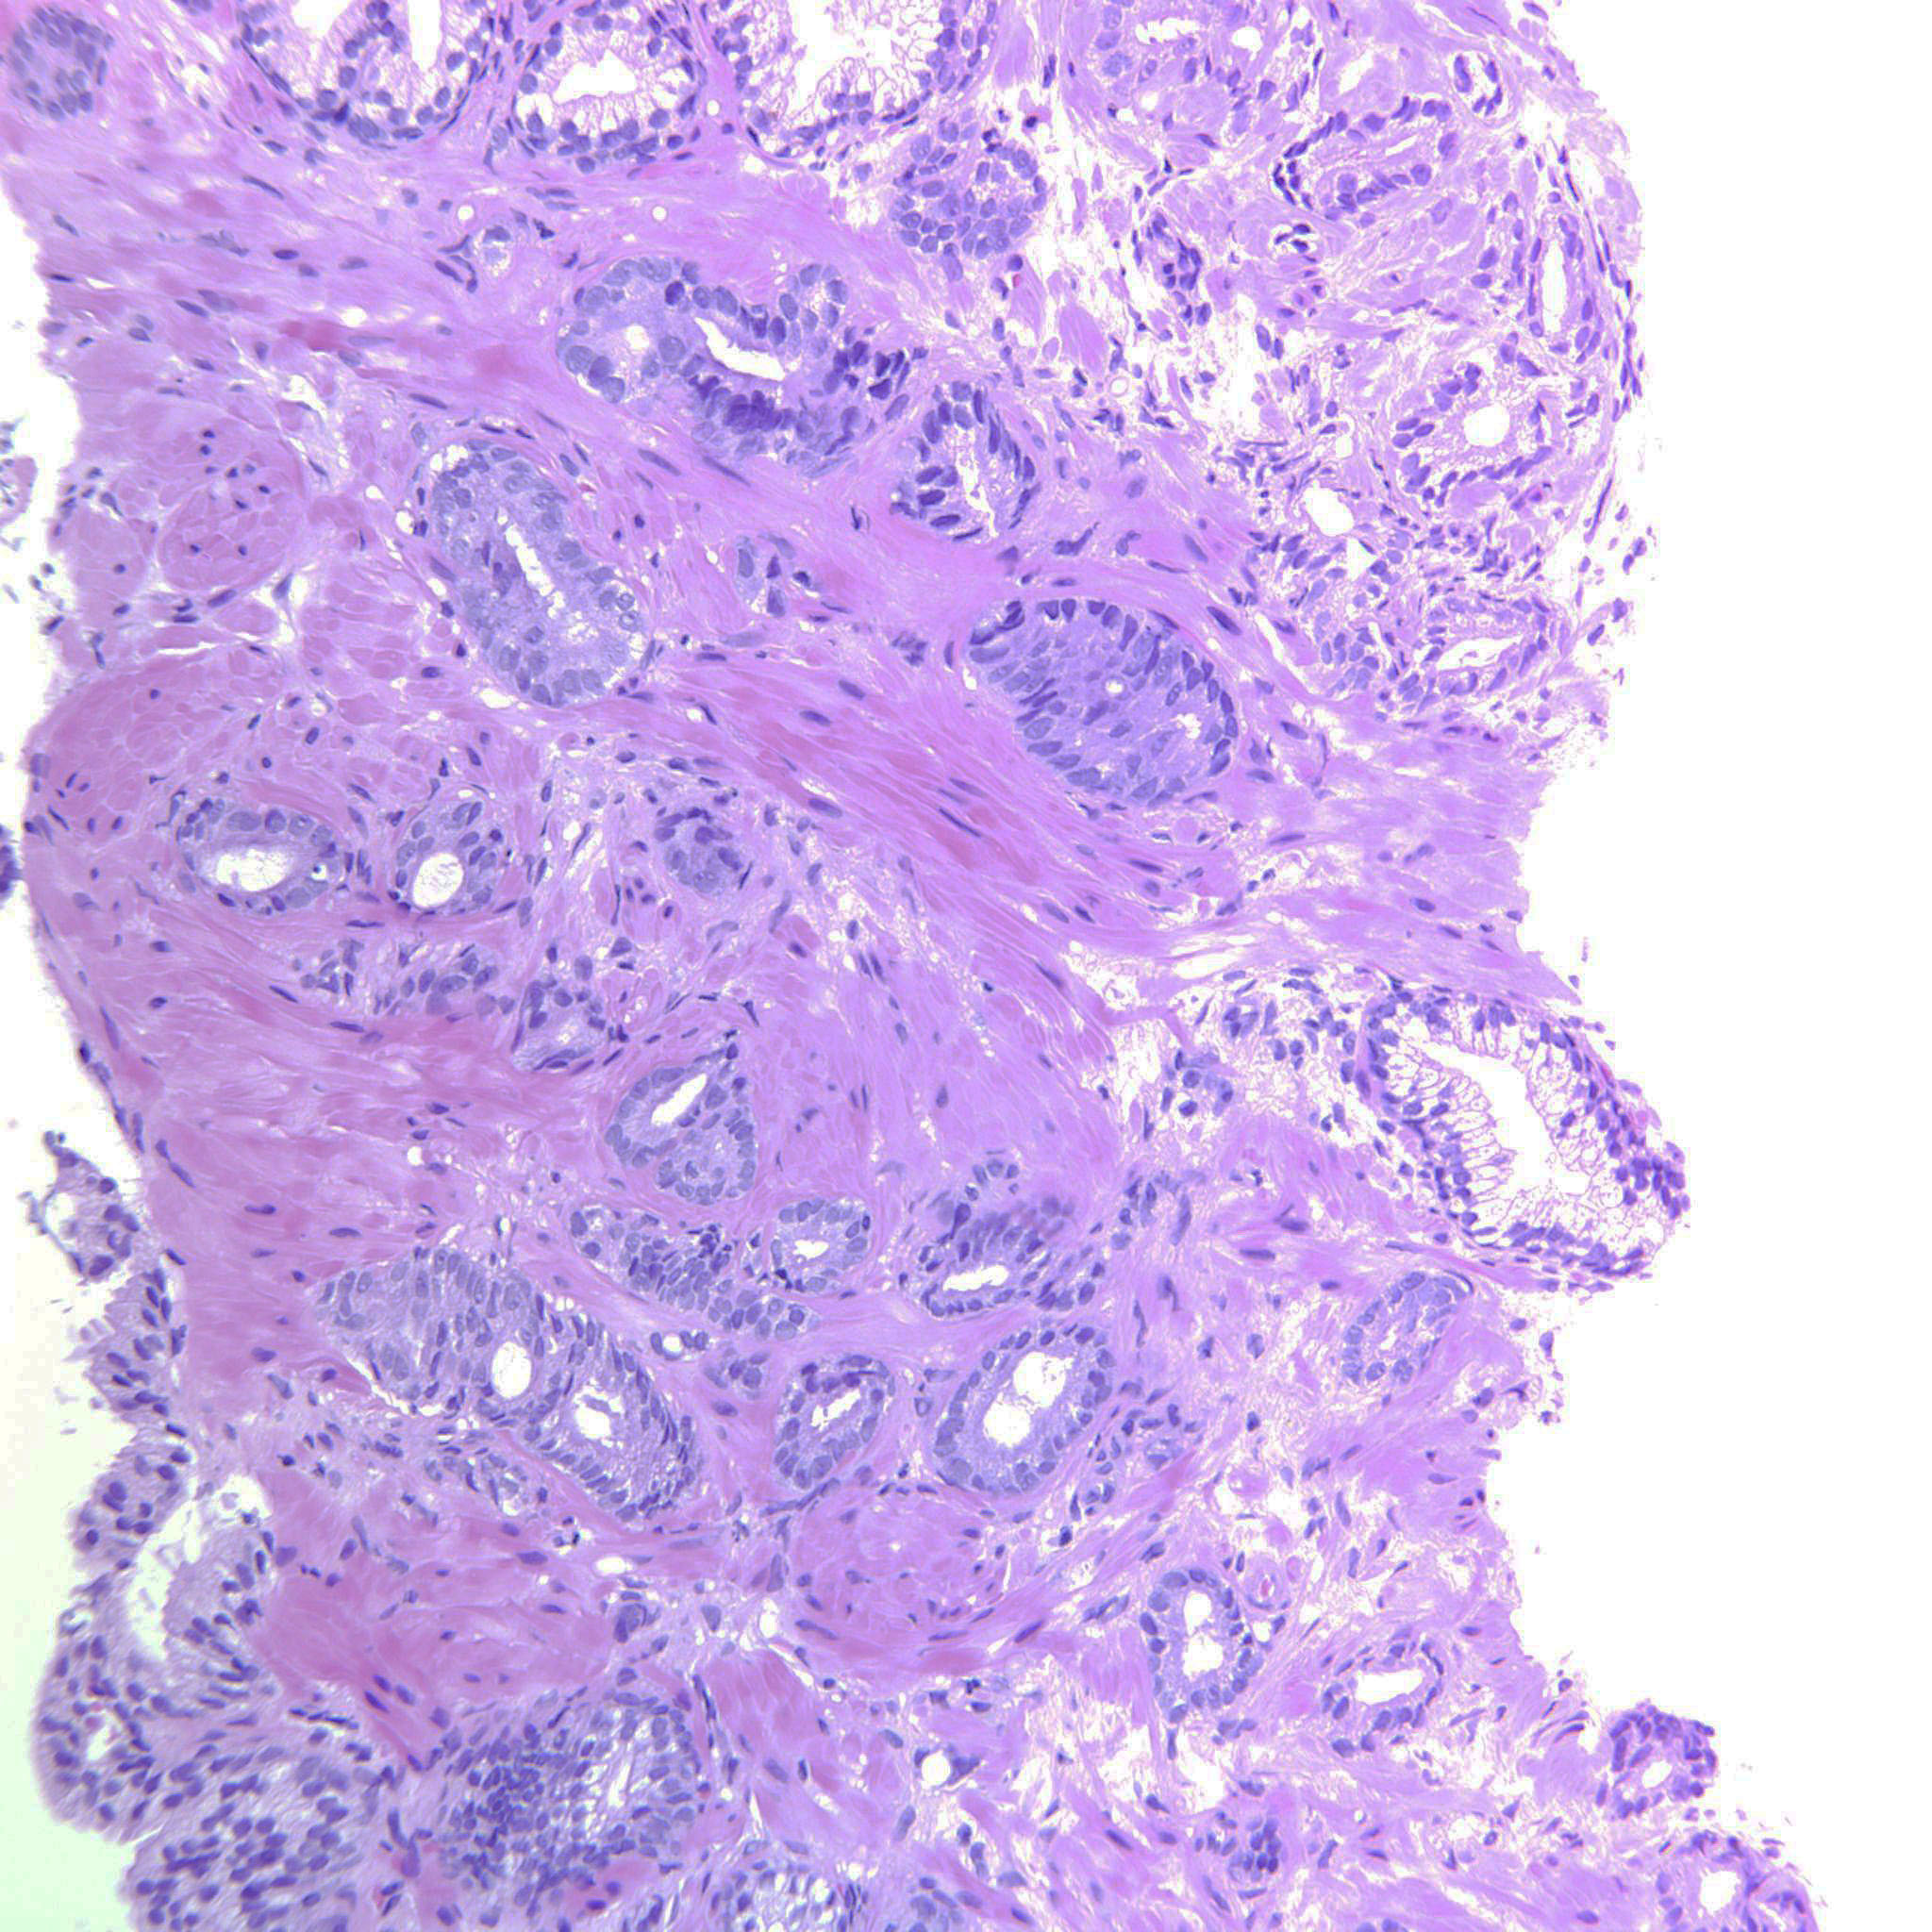

Prostate cancer grading

Case ID: 643